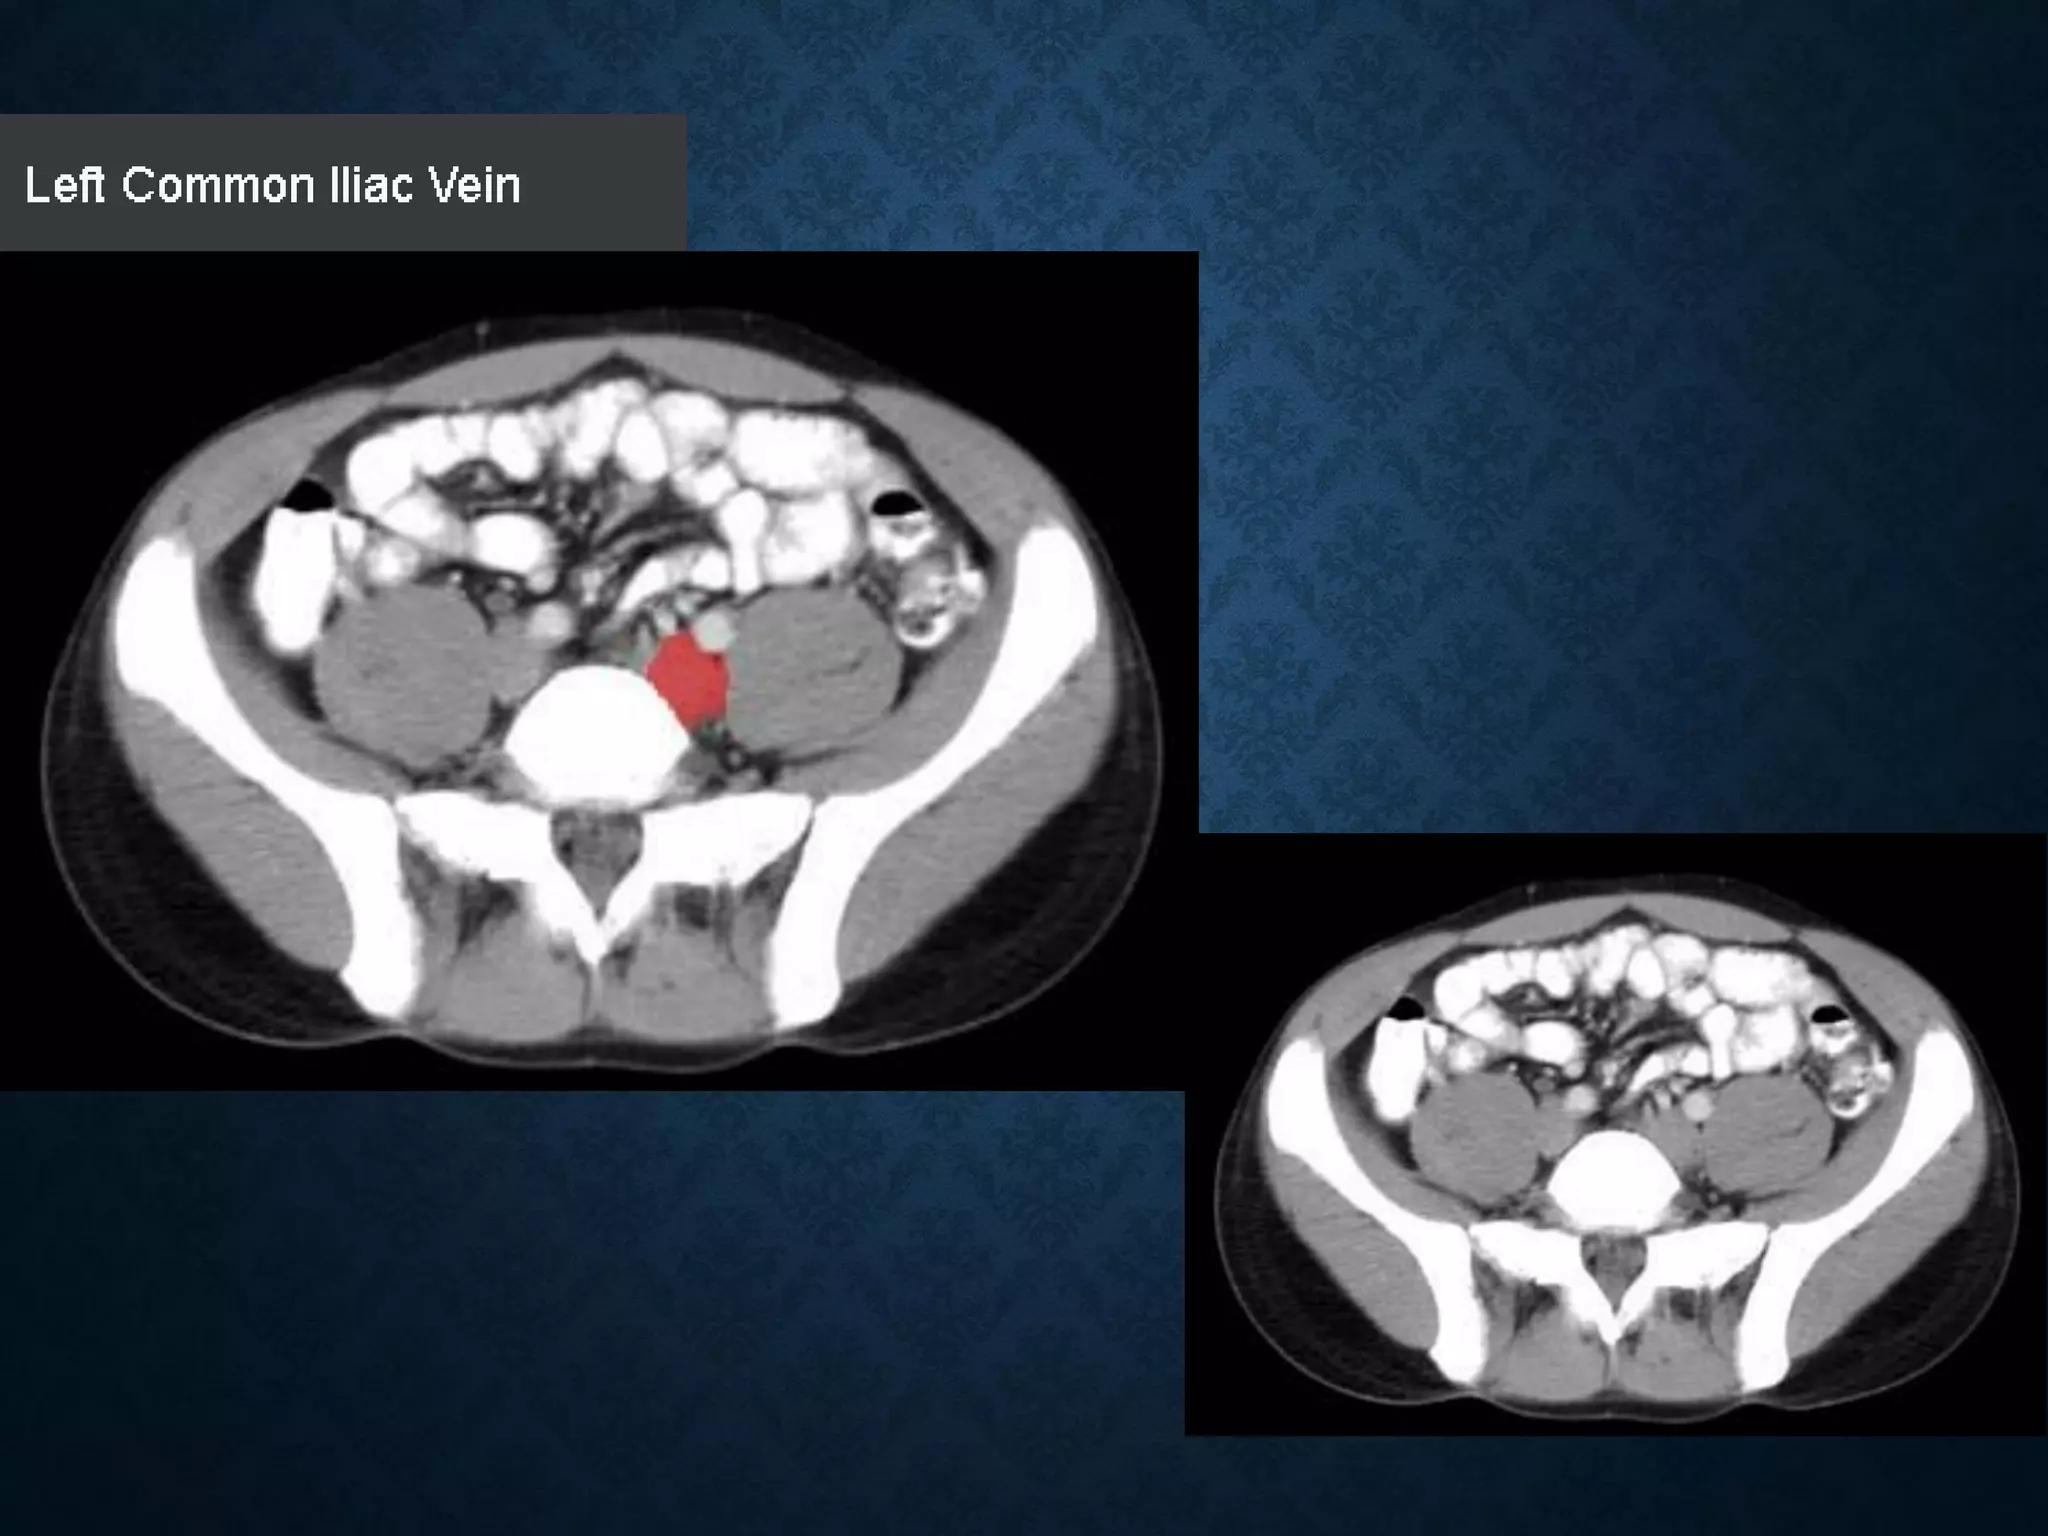

SUPERIOR MESENTERIC VEIN

• In anatomy, the superior mesenteric vein (SMV) is a blood vessel

that drains blood from the small intestine (jejunum and ileum).

• At its termination behind the neck of the pancreas,

• the SMV combines with the splenic vein to form the hepatic portal vein.

• The SMV lies to the right of the similarly named artery, the superior

mesenteric artery, which originates from the abdominal aorta.

SUPERIOR MESENTERIC VEIN •In anatomy, the superior mesenteric vein (SMV) is a blood vessel that drains blood from the small intestine (jejunum and ileum). • At its termination behind the neck of the pancreas, • the SMV combines with the splenic vein to form the hepatic portal vein. • The SMV lies to the right of the similarly named artery, the superior mesenteric artery, which originates from the abdominal aorta.